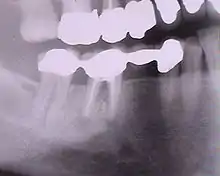

Radiographie des six implants